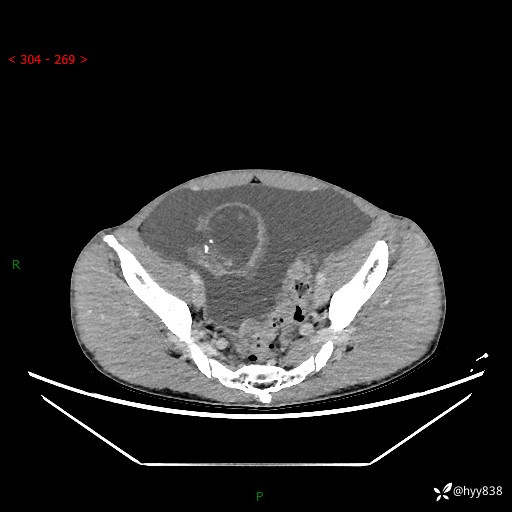

现病史:患者10天前无明显诱因出现腹部胀痛不适,无畏寒发热,无胸痛胸闷,无心慌气短,无恶心呕吐,无腹泻及黑便,无粘液血便及里急后重等症状,4天前在当地县人民医院就诊,行腹部CT示:下腹部占位性病变,腹腔及盆腔积液;今患者为求进一步诊治来我院治疗,门诊以“腹水”收治入院。 发病以来,精神饮食可,大小便正常,体重体力无明显变化。

腹部CT平扫+增强